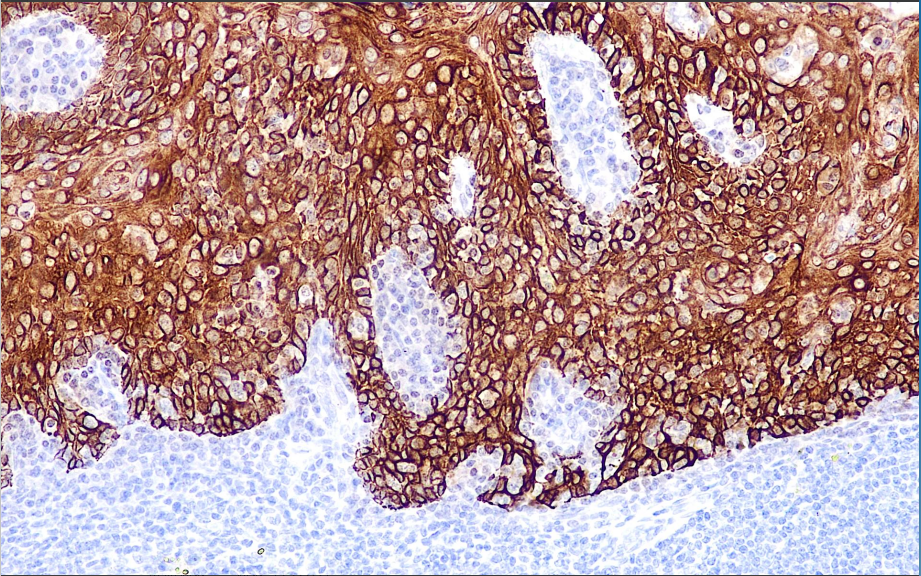

CK5 is expressed in basal cells of squamous epithelium and ductal epithelium, as well as in some squamous epithelial germinal layer cells, myoepithelial cells, and mesothelial cells in normal tissues, while the vast majority of glandular epithelial cells exhibit minimal expression. Therefore, it can be used for research on squamous cell carcinoma, adenocarcinoma, mesothelioma, and adenocarcinoma. It can also be used for research on benign and malignant tumors of epithelial origin in the breast, salivary glands, and prostate.

CK5 antibody reagents can specifically bind to CK5 molecular antigens. Immunohistochemistry kits containing CK5 antibody reagents are suitable for the auxiliary diagnosis of squamous cell carcinoma, adenocarcinoma, mesothelioma, and other diseases.